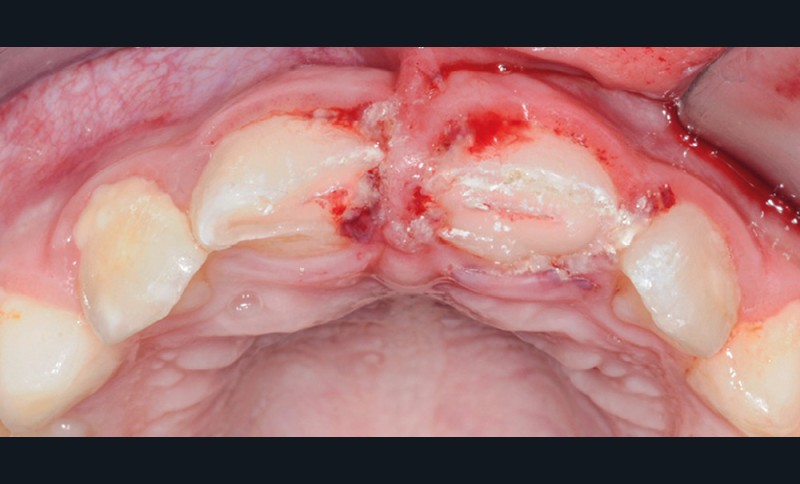

- une plaie au niveau du frein labial supérieur ;

- une fracture corono-radiculaire avec effraction pulpaire de 11 et 21 (fig. 1 et 2) ;

- une subluxation de 11 et 21 (saignements sulculaires).